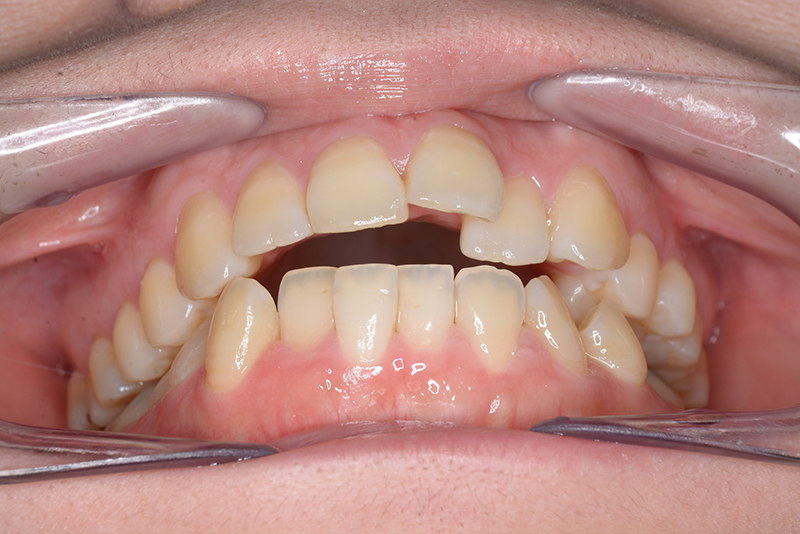

| 主訴 | 前歯で物が噛めない | 診断名 | アングルⅠ級開咬症例 | ||||

|---|---|---|---|---|---|---|---|

| 初診時年齢 | 37歳8ヵ月 | 性別 | 女 | 動的治療期間 | 23ヵ月 | ||

| 口腔内所見 | 臼歯関係はⅠ級、over jet 4.5mm、over bite -3.0mm。上下顎切歯部に軽度の叢生が認められ唇側傾斜をしつつ開咬を呈していた。 |

| 批評・予后 | 治療後において下顎角の開大も認められず歯軸の整直、咬合の緊密化が得られた。また上下顎前歯の後退と共に口元の突出感と口唇閉鎖不全の改善が認められた。 |